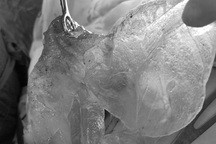

Ca phẫu thuật tái tạo ngực cho bệnh nhân diễn ra trong 6 giờ đồng hồ (Ảnh: BV).

Ngày 11/2, ca phẫu thuật tái tạo ngực chính thức diễn ra. Ekip điều trị cẩn thận thực hiện chuyển vạt cơ bụng lên ngực nhằm tái tạo phần bầu ngực đã mất. Song song đó, các bác sĩ cũng thực hiện bóc tách sẹo ở nách, để bệnh nhân có thể cử động dễ dàng hơn. Sau 6 giờ ròng rã, ca phẫu thuật kết thúc khi trời đã tối muộn.